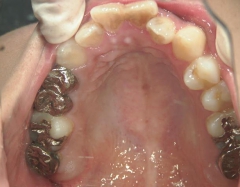

矯正歯科 治療前矯正歯科 治療前

矯正歯科 治療前 上顎を装置(QH)で拡大後ワイヤー矯正へ移行、右下5番左下4番 計2本抜歯叢生改善

矯正_灰色.pngno.28_6958_治療前_上.jpg矯正_灰色.png